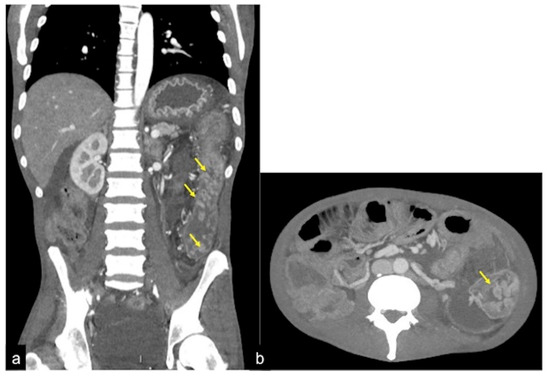

| Angiodysplasia (Figure 11) | Obscure bleeding. | Abnormally dilated, tortuous, thin-walled vessels involving small capillaries, veins and arteries. |

| Angiodysplasia (Figure 5 and Figure 34) | Asymptomatic or bleeding. | Small hyperdense nodules within the intestinal wall, best defined in the portal phase of the study. |